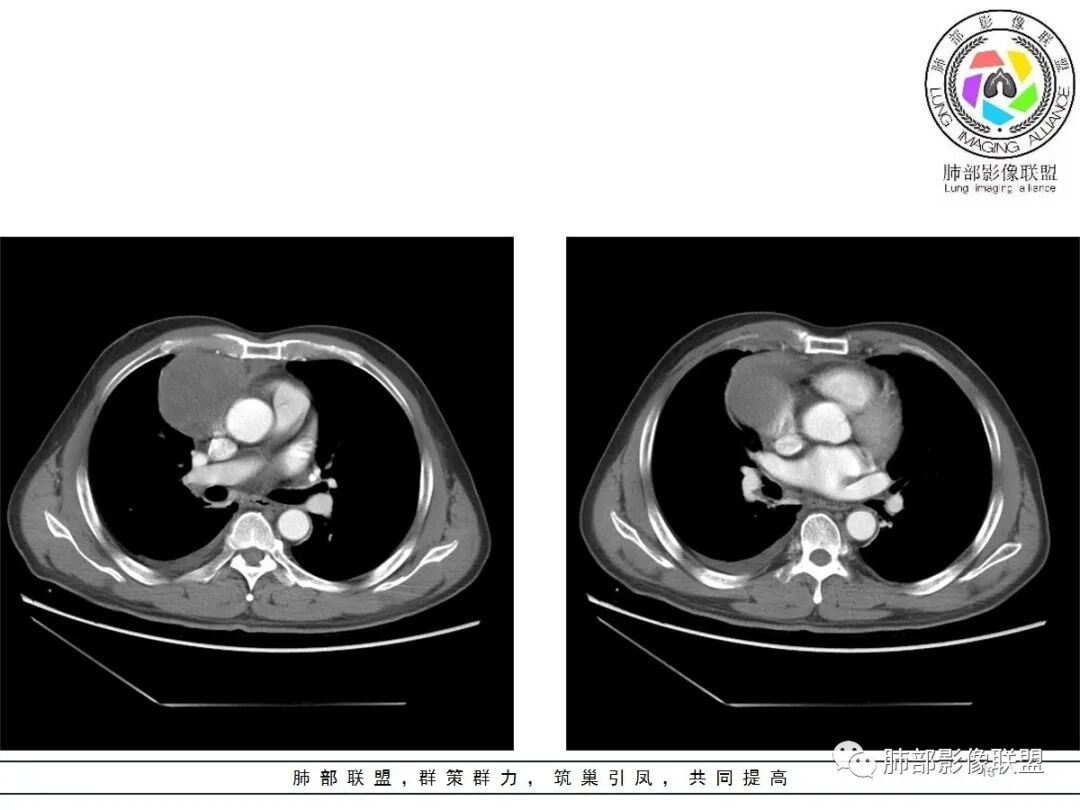

大雄:老年男性  急性起病 胸痛1天前纵隔占位伴右侧少量胸水,肿块整体膨隆,密度不均匀,可见坏死,纵隔脂肪间隙模糊不清常规考虑胸腺瘤/癌并梗死

一切∮随缘:定位肺外,病变位于右前纵隔,与肺部交接面清晰,有胸膜尾征,心包局部受压,部分包绕主动脉血管,平扫密度均匀,形态规则,膨胀性生长,增强扫描壁有强化,内容物无明显强化,考虑1:淋巴瘤2:胸腺瘤3:神经鞘瘤4:支气管囊肿

亚东:前纵隔囊实性肿物,形态尚规则 ,与心包分界不清,内可见小气泡,嚢内平扫密度低,强化不明显,囊壁强化,右胸腔积液,淋巴结肿大不明显,化验白细胞高,支持囊肿伴感染。

小强:前纵隔肿块,边缘模糊,其内有点状气体影,环形强化(肉芽肿?),心包胸膜受累,疾病谱:胸腺瘤(一般是侵袭性胸腺瘤累计心包,胸膜,强化不符合)淋巴瘤,生殖细胞瘤(年龄,AFP不高不负),考虑畸胎瘤,囊性畸胎瘤合并感染,边缘模糊,累计心包胸膜,3.19病变进展,胸腔积液,可能有破溃

采莲:老年男性,胸疼病史,右上前纵隔肿块,边缘光滑,平扫内部密度稍均匀,轻度强化,内有低密度区,与支气管关系不大,右侧少量积液。考虑来源纵隔,老年男性,胸腺瘤或胸腺癌,鉴别淋巴瘤。

修*:前纵隔偏右侧肿物,点状钙化,轻度强化,伴胸腔积液,考虑胸腺瘤B2型。

岁月:男性,68岁,右胸痛一天,无家族史,右上中叶纵膈旁占位;抽烟50年,3天1包。wbc高。与纵膈脂肪间隙不清,胸水,快进快出 分叶,有血管样强化,9.1-11.4-10.9。诊断:错构瘤,似乎都符合;但如果恶性放在前面,肉瘤、恶性。鉴别:错构瘤、侵袭性胸腺瘤;处理:经皮肺活检、手术。

王秀仙:右侧前纵膈肿块,密度不均,局部边缘可见点状钙化,其内可见点状低密度,与纵膈血管间脂肪间隙消失模糊,右侧胸腔积液,考虑纵膈畸胎瘤或皮样囊肿破裂。鉴别胸腺鳞癌。

必有路:老年人,右前纵隔占位,发病前纵隔脂肪干净,突发起病伴胸痛,白细胞增高病灶整体密度较为均匀,内有点状脂肪密度,位置个人觉得理胸腺区有点偏下,大部分囊性为主1、胸腺瘤伴突发梗死  突发起病,老年男,不支持点,位置偏下,囊变坏死太彻底,右侧胸廓内动脉没有增粗(实性肿瘤,往往会有间接供血增粗)倾向支持囊性病灶合并破溃感染2、囊性畸胎瘤伴破溃  影像上可以支持,脂肪含量比较少,发病年龄不太支持3、 皮样囊肿 可以有脂肪密度4、 支气管囊肿 理论上胸廓内都可以发生,肺内 后纵隔多见 张力大 圆5、心包囊肿  中纵隔更为多见综上,皮样囊肿>囊性畸胎瘤>胸腺瘤

肿瘤样病变破裂所致纵隔炎应该没错

南边:肿瘤或肿瘤样病变破裂所致纵隔炎,这是大方向

结果:符合B型胸腺瘤伴出血,坏死囊性变,局部脓肿形成